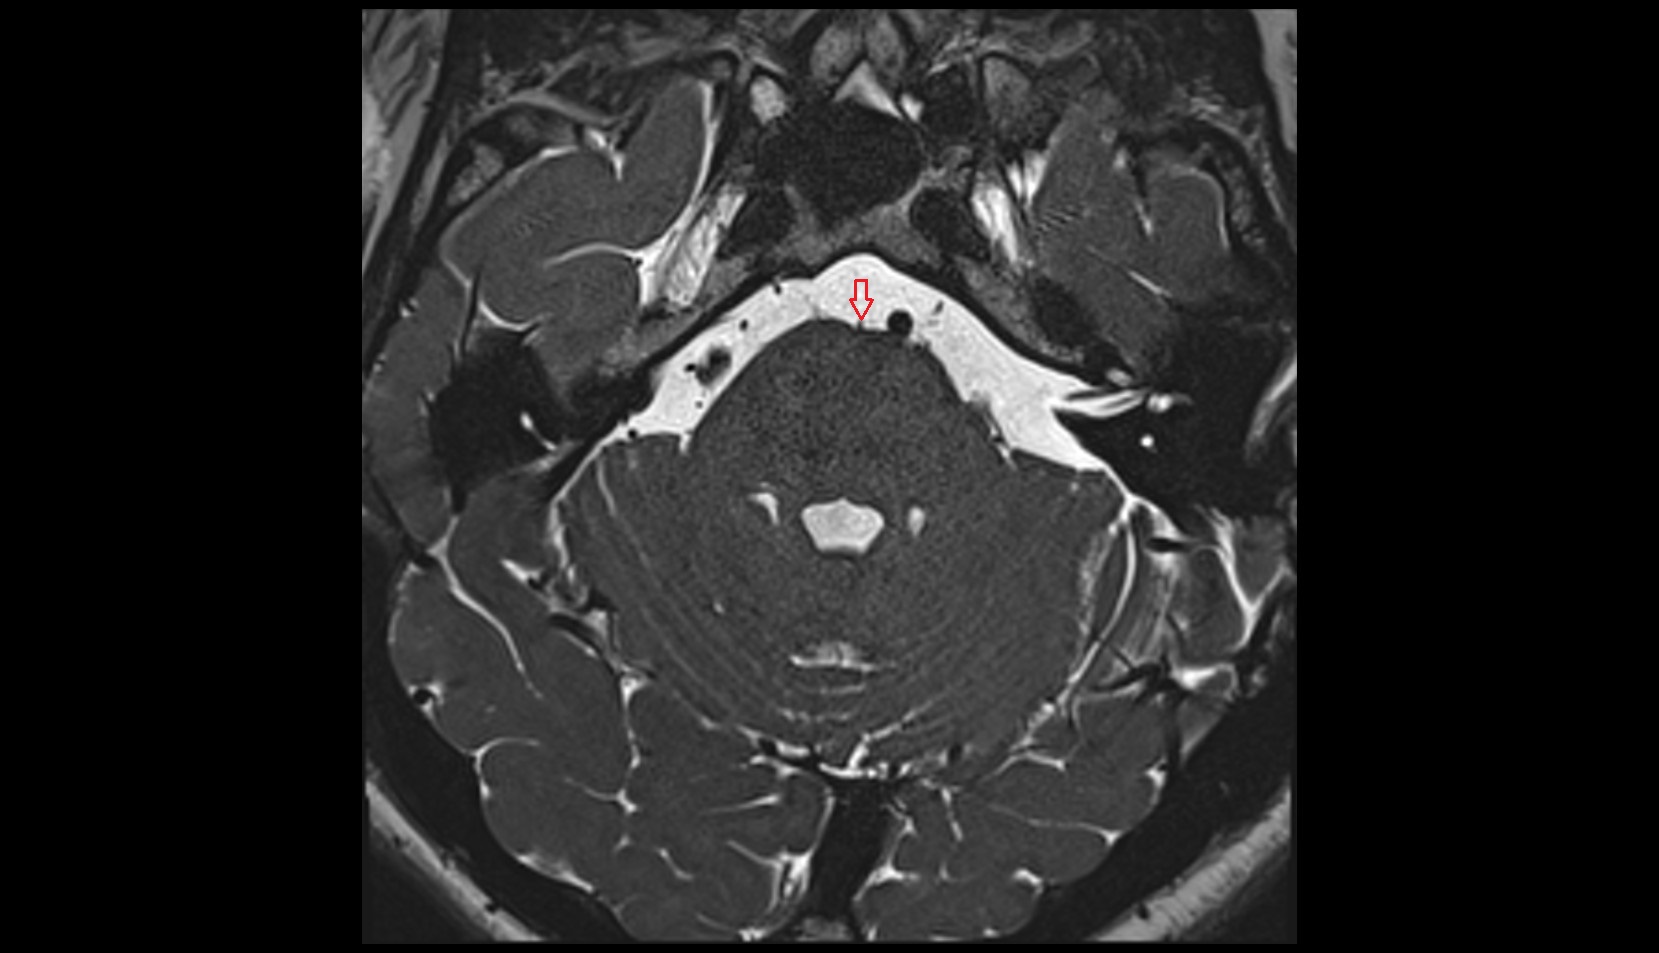

- Peripheral zone of prostate

- Anterior Fibromuscular Stroma of prostate

- Central zone of prostate

- Transitional zone of prostate